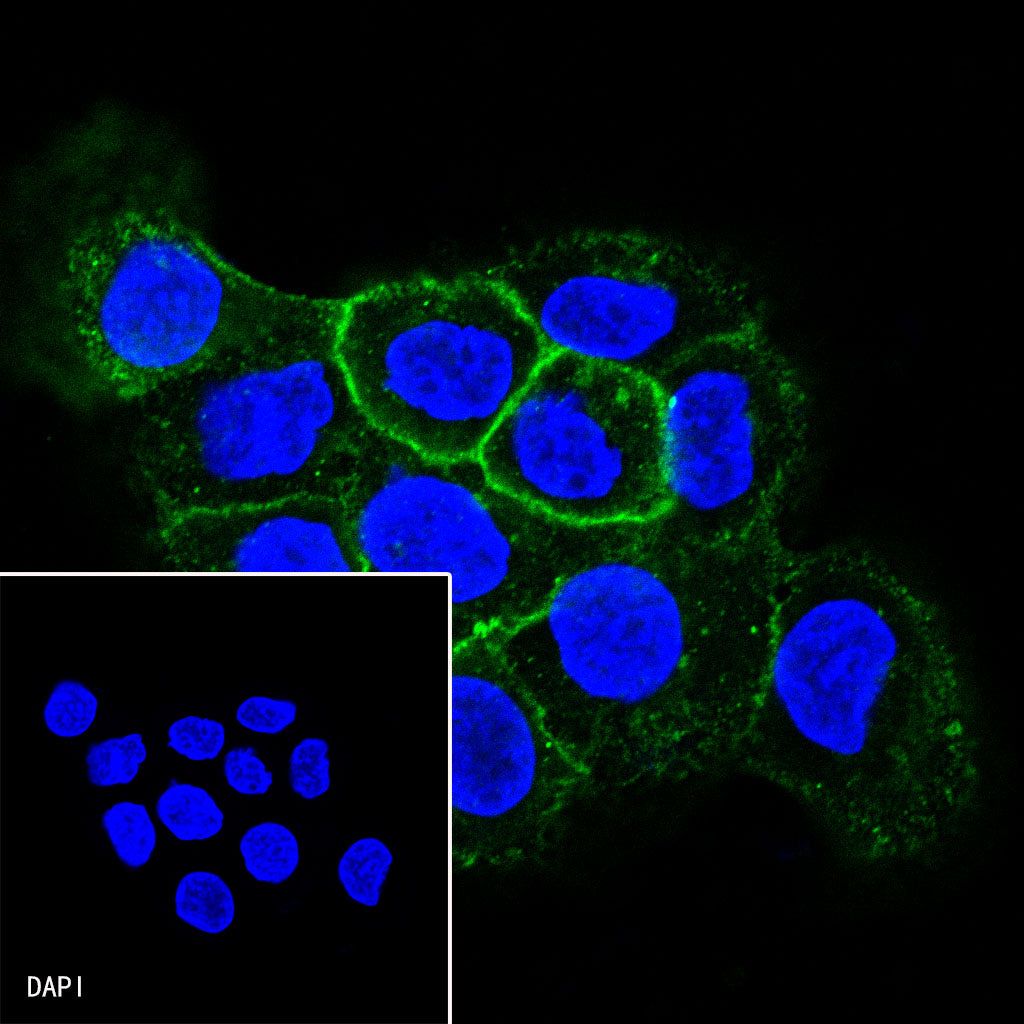

Immunocytochemistry

ICC shows positive staining in A431 cells. Anti-CD138 antibody was used at 1/25 dilution (Green) and incubated overnight at 4°C. Goat polyclonal Antibody to Rabbit IgG - H&L (Alexa Fluor® 488) was used as secondary antibody at 1/1000 dilution. The cells were fixed with 100% ice-cold methanol and permeabilized with 0.1% PBS-Triton X-100. Nuclei were counterstained with DAPI (Blue).

Negative control:ICC shows negative staining in Jurkat cells. Anti-CD138 antibody was used at 1/25 dilution and incubated overnight at 4°C. Goat polyclonal Antibody to Rabbit IgG - H&L (Alexa Fluor® 488) was used as secondary antibody at 1/1000 dilution. The cells were fixed with 100% ice-cold methanol and permeabilized with 0.1% PBS-Triton X-100. Nuclei were counterstained with DAPI (Blue).